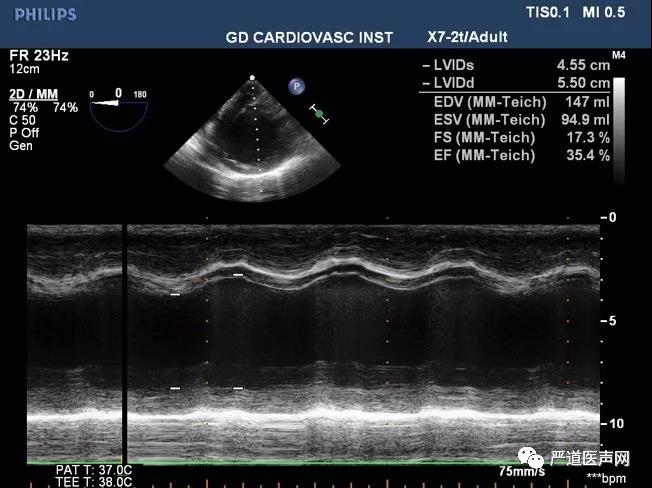

术前全麻状态下LVEF 17.7%

术后即刻LVEF 35.4%,较术前显著改善